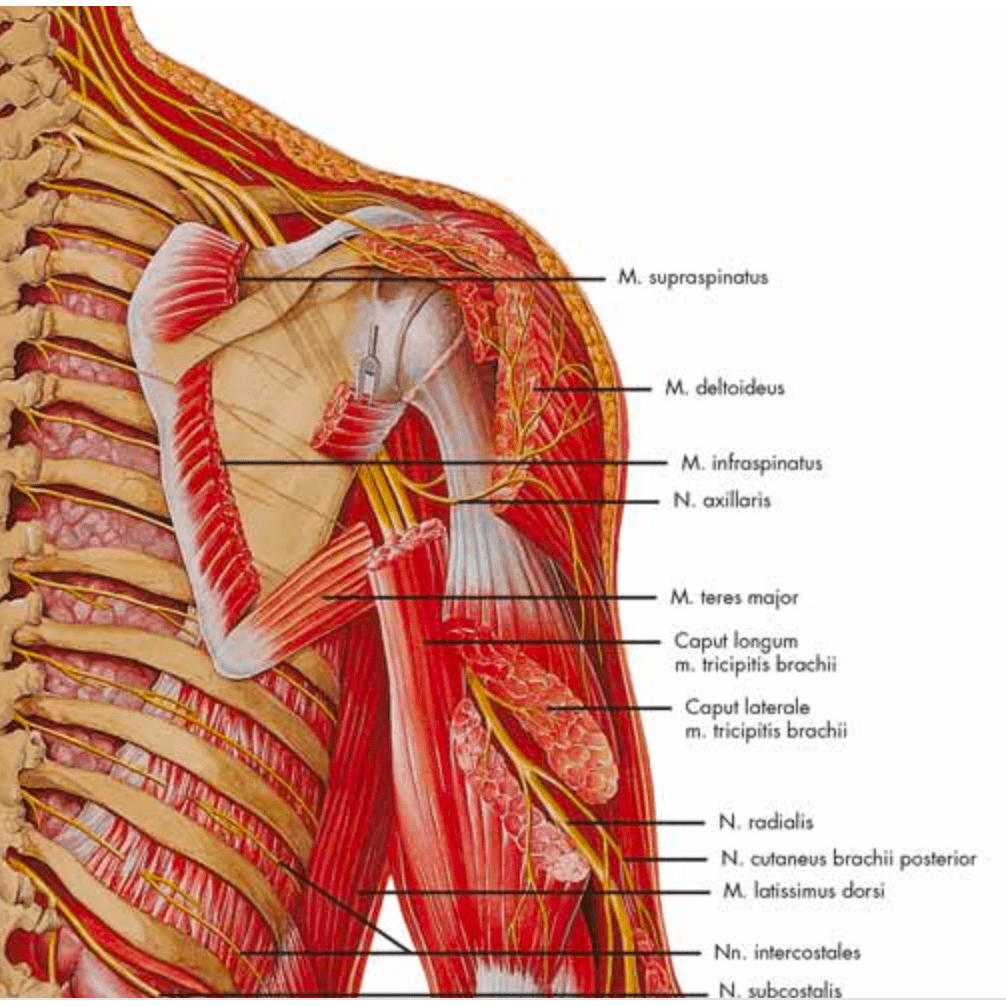

Muscle posters

Muscles provide movement to the musculoskeletal system, and their origins, insertions and lodges are clinically important for every healthcare professional. That is why we at eAnatomi have both developed and designed our own anatomy posters, which provide the ultimate overview of all the muscles of the body. On this page you can find both our own posters and posters from other manufacturers. We offer posters in several different languages such as pure Latin, Danish, English and Swedish, etc.